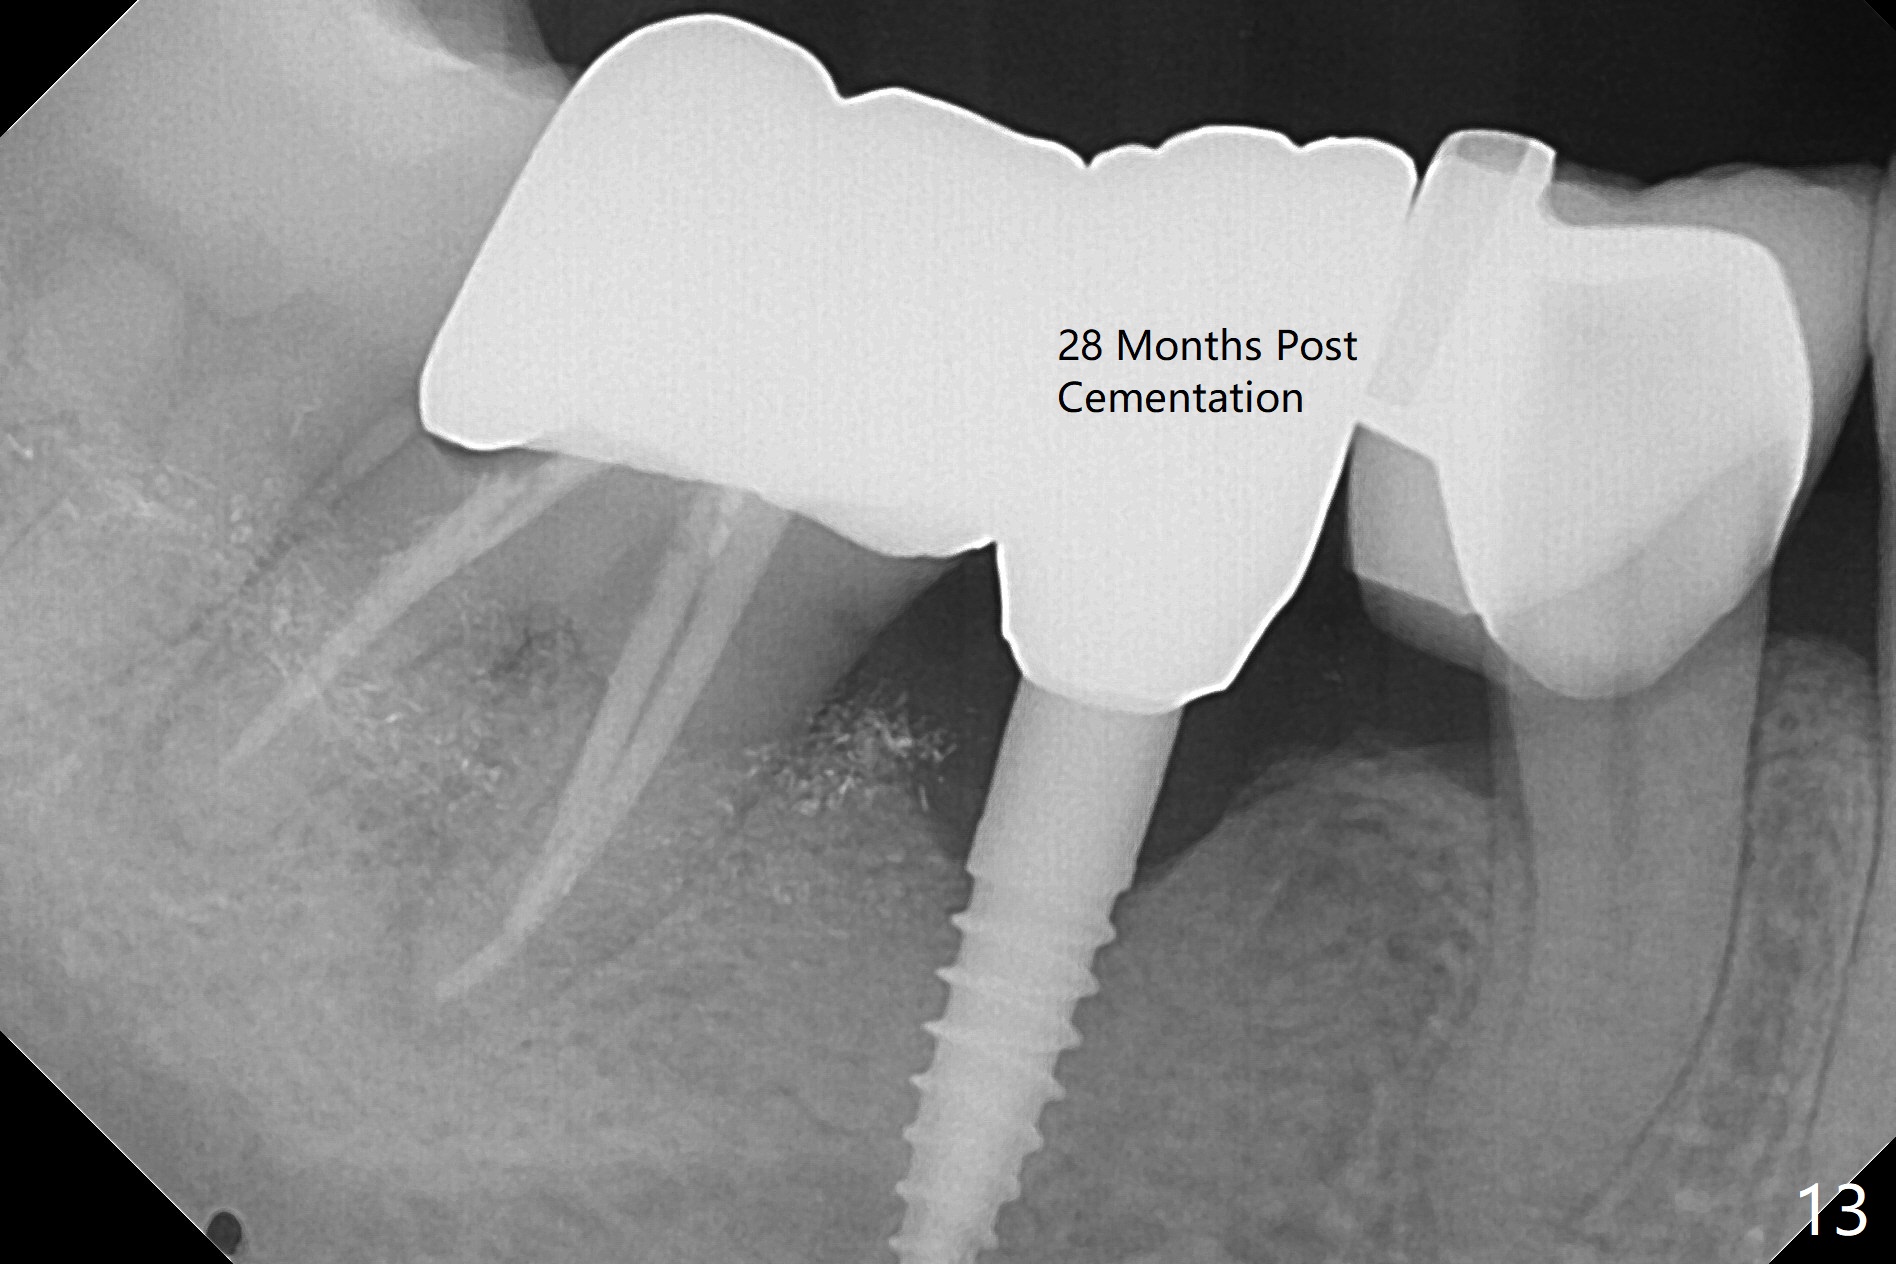

There is a space underneath the pontic at #30 (Fig.1 *), the basis for food impaction. After sectioning between the pontic and the posterior retainer, the pontic is removed from the anterior retainer with an attachment (Fig.2 *). The initial depth of osteotomy is 10 mm following ridge top reduction (Fig.3). A 3x10(4) mm 1-piece implant is placed with >50 Ncm; to reduce possibility of crown dislodgement from the implant, the retainers will be kept with modification of the proximal surfaces as shown by curved lines in Fig.4. Periodontal dressing is applied after suturing. There is no postop paresthesia. The periodontal dressing remains in place 2 weeks postop because of engagement into the attachment slot and undercuts (Fig.5). The patient returns 3 months postop; after minor contour adjustment (Fig.6 red curved line), impression is taken. The permanent crown is temporarily cemented (3.5 months postop) in case of food impaction due to the distal overhang of the tooth #29 (Fig.7). In fact the patient returns 4.5 months post cementation with right TMD (muscle relaxant prescribed) and food impaction, although there is no bone resorption (Fig.8,9). It appears that the crown at #29 needs to be redone, while porcelain will be added to the mesial surface of the one at #30 (Fig.10 red lines). In fact the crown at #30 is redone because of loose proximal contact with #31; there is no bone resorption 13 months post cementation (Fig.11). Bone resorption remains unnoticeable 28 months post cementation (Fig.12,13).